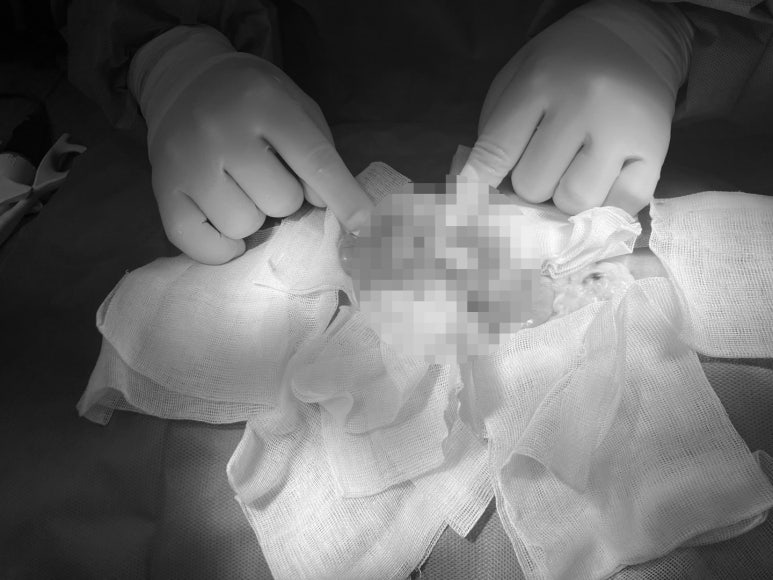

수혈로 어느 정도 상태를 끌어올린 뒤, 막힌 장을 해결하기 위해 지체 없이 응급 개복 수술(장 문합술)에 들어갔습니다.

▲ 개복 후 확인한 장의 모습입니다. 초음파에서 본 것처럼 장의 한 부분이 다른 장 안으로 깊게 말려 들어가 심하게 부어있는 것을 확인할 수 있습니다.

▲ 중첩된 장을 조심스럽게 빼내어 확인하는 모습입니다.

어린 고양이들의 장중첩은 심한 장염이나 기생충 때문에 생기기도 하지만, 노령묘에서 장중첩이 발생했다면 장벽에 생긴 종양이 원인일 가능성이 매우 높습니다. 장벽에 자리 잡은 종양 덩어리가 비정상적인 장의 연동 운동을 유발하여 장이 서로 겹쳐 말려 들어가게 만드는 것이죠.

수술 중 확인해 보니 역시나 중첩된 장 부근에서 두 개의 뚜렷한 종괴가 발견되었습니다. 저희는 문제가 발생한 장 부위를 안전하게 절제하여 문합하는 수술을 무사히 마치고, 잘라낸 종양 덩어리는 정확한 진단을 위해 외부로 조직 검사를 의뢰했습니다.